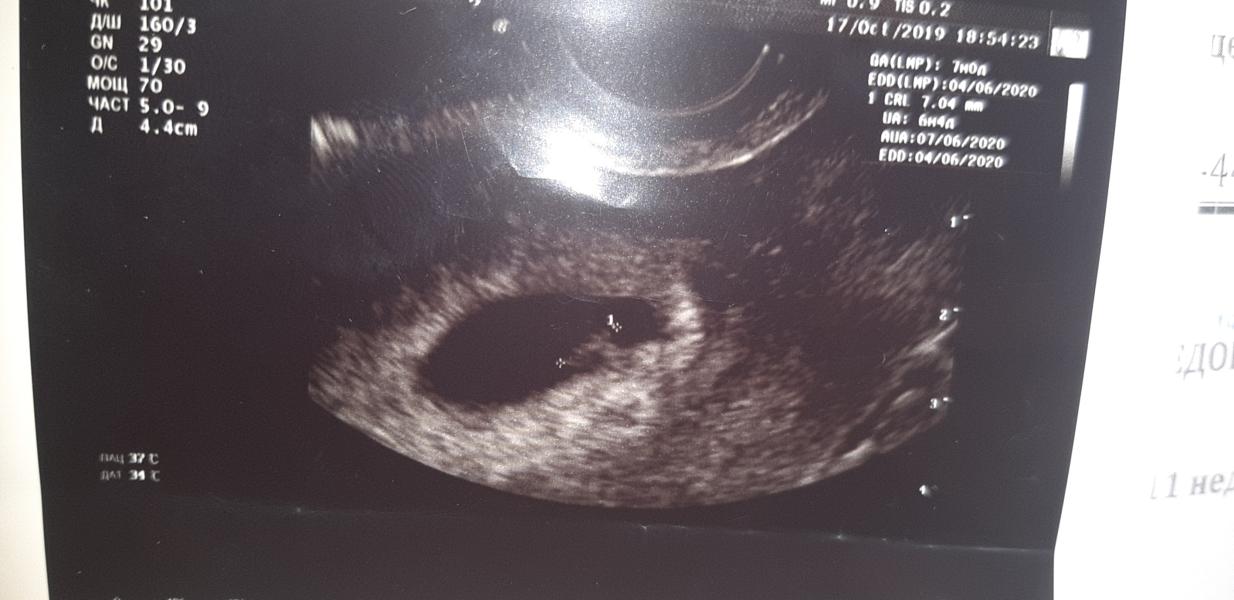

Неделю назад на узи не нашли эмбриона. Сегодня все отлично сердце +. Расти крошка.🥰🥰🥰 #первыйпост